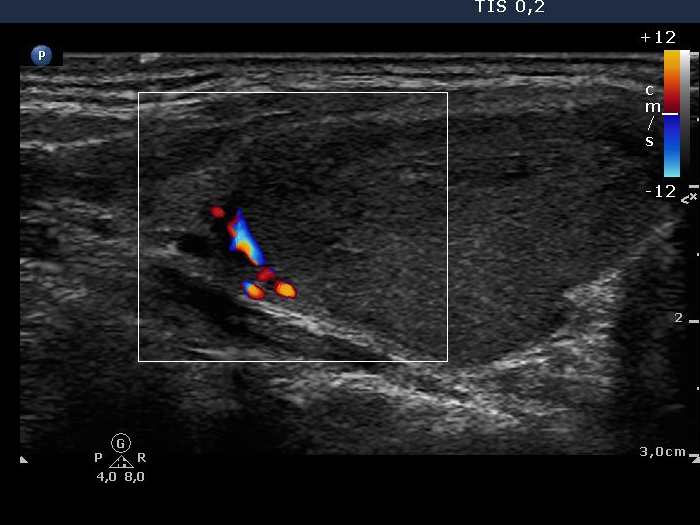

Follicular carcinoma - Case 3. (ultrasound picture 4)

Right lobe, longitudinal scan, color Doppler mode. Signs of perinodular blood flow.